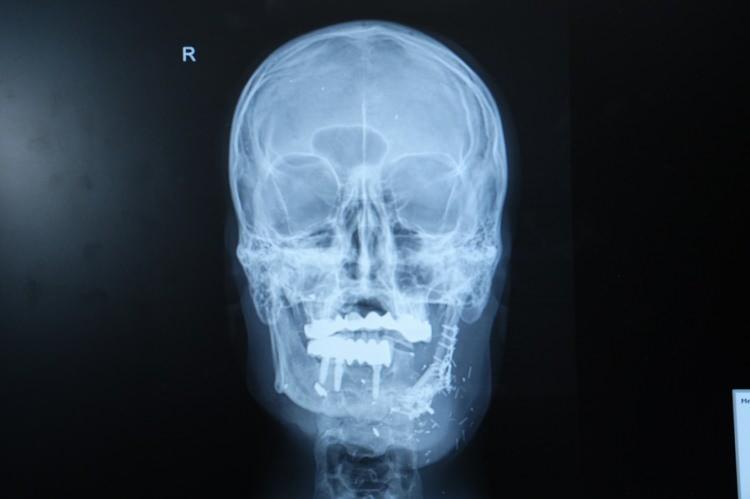

Ateşli silah yaralanması nedeniyle çenesinin yarısını kaybeden ve hayatı kâbusa dönen İzzet Baldır, Plastik ve Rekonstrüktif Cerrahi Uzmanı Doç. Dr. Burak Özkan’ın gerçekleştirdiği operasyonla sağlığına yeniden kavuştu. İşte o operasyon...

Ateşli silah yaralanması sonrası çenesinin yarısını kaybeden İzzet Baldır, daha önce farklı merkezlerde ameliyat olmuş fakat nakiller başarısız olmuştu.